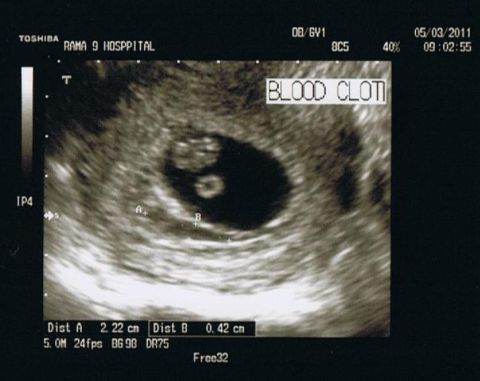

Гематома при беременности на ранних сроках может существенно ухудшить прогноз . Каковы причины развития этой патологии? Как проводится лечение ретрохориальной и субхориальной форм в матке?

Ретрохориальная гематома при беременности, выявленная на ранних сроках и на начальной стадии развития легко поддается терапии и зачастую рассасывается к третьему триместру .

Следствием этого стало решение обратиться в платную клинику для проведения диагностики . Анализ показал наличие гематомы в матке при беременности на ранних сроках размером 13*8 мм .

Гематомы на ранних сроках: причины и осложнения Гематомы при беременности иногда обнаруживаются после проведения УЗИ .